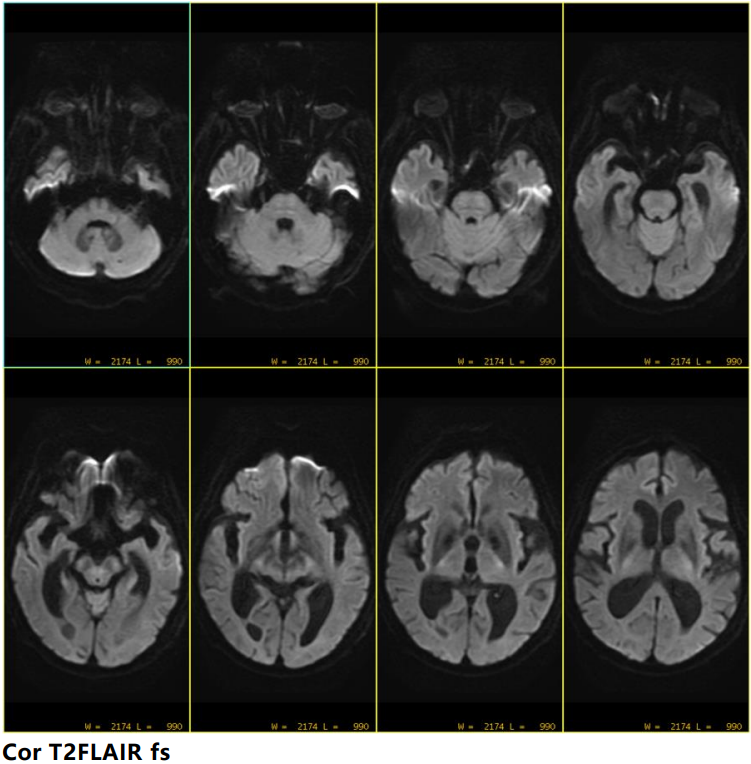

不出意料,看不见啥。 来点科技与狠活:Ax DWI b1000 书接上一期,有网友回复,DWI要额外收费。小编也在医院工作过5年,当年也和诊断老师讨论过DWI收费的问题。很多时候,一旦收费,临床医生可能漏开,更有可能为了减轻患者负担不开。DWI对于急性脑梗死的意义,无需赘述。而且只需要十几秒就可以完成颅脑DWI扫描,并不会显著影响扫描效率。所以,笔者当年的医院,所有颅脑扫描都含DWI。所谓我为人人,人人为我。

随着b值升高,中脑病灶信号增高,ADC亦见明显低信号 大海捞针最终找到了病灶。 临床不再因MRI未见异常而不知如何是好。 四、常规AX DWI为什么难以发现脑干梗死 最近几年,陆陆续续有几篇SCI文章提示,AX DWI难以发现脑干梗死,必要时建议增加SAG 或者COR DWI,甚至使用更高b值,便于发现更隐匿的梗死病灶。